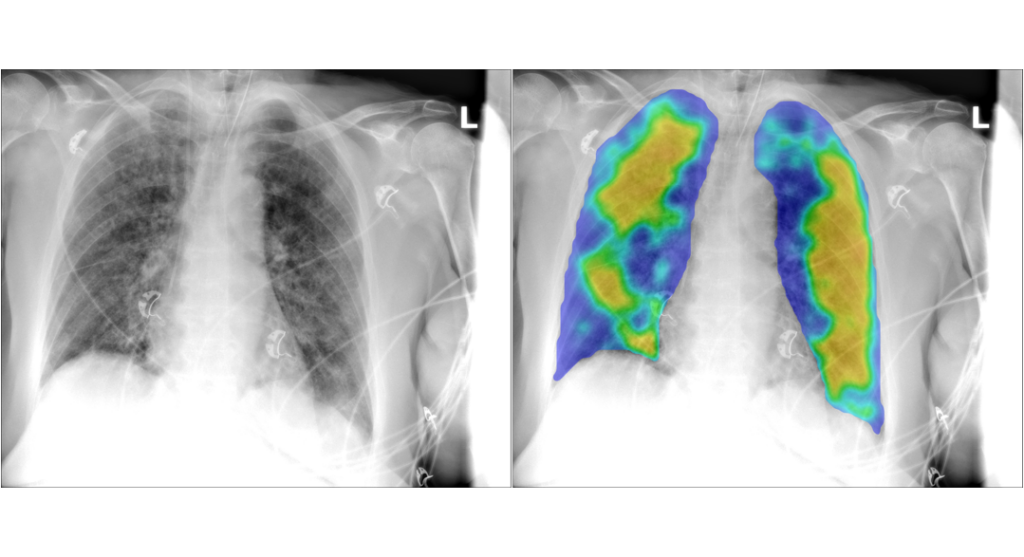

CAD4COVID-XRay performs comparable to radiologists

Artificial intelligence tool CAD4COVID-XRay can perform comparably to radiologists in triaging suspected COVID-19 cases by analysing chest X-rays.

Triage for COVID-19 Using AI on Chest X-rays

Thirona has screened over 6 million people in 40 countries with its proven CAD4TB solution.